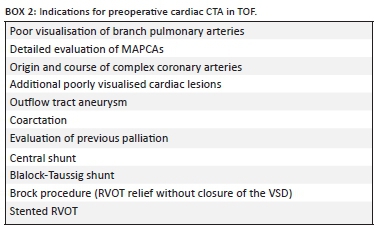

Cardiac CTA provides the ideal alternative to invasive and potentially hazardous cardiac catheterisation when the limitations of echocardiography fail to meet the goals of imaging.12 Box 2 illustrates the indications for preoperative cardiac CTA in TOF.